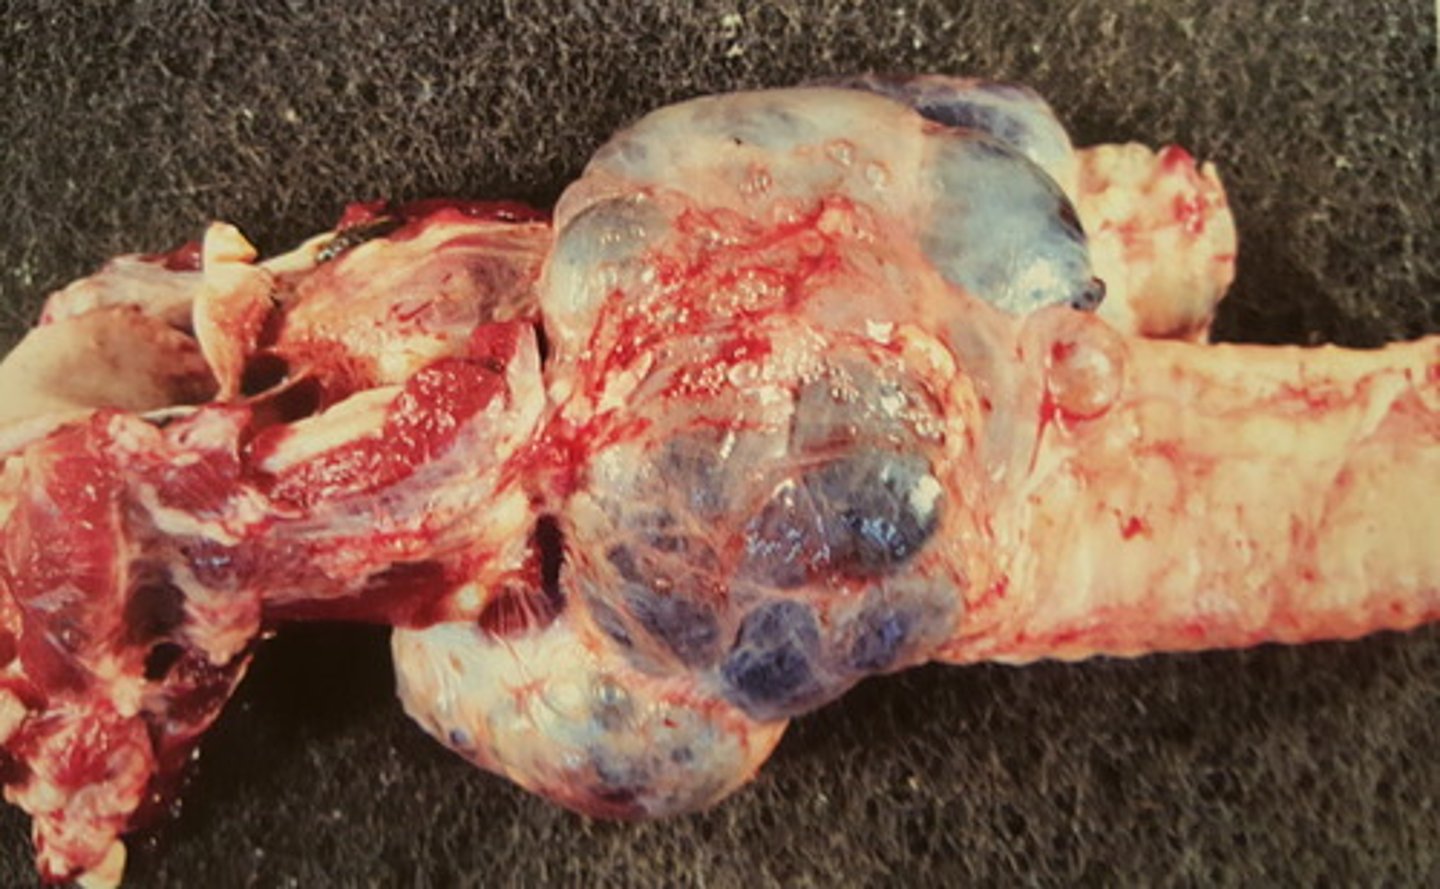

Kronisk peritoneal og perihepatisk cystecerkose

Ætiologi: Cysticerus tenuicollis

Lever fra får (med diaphragma, D), hvad er den patoanatomiske diagnose og ætiologien?